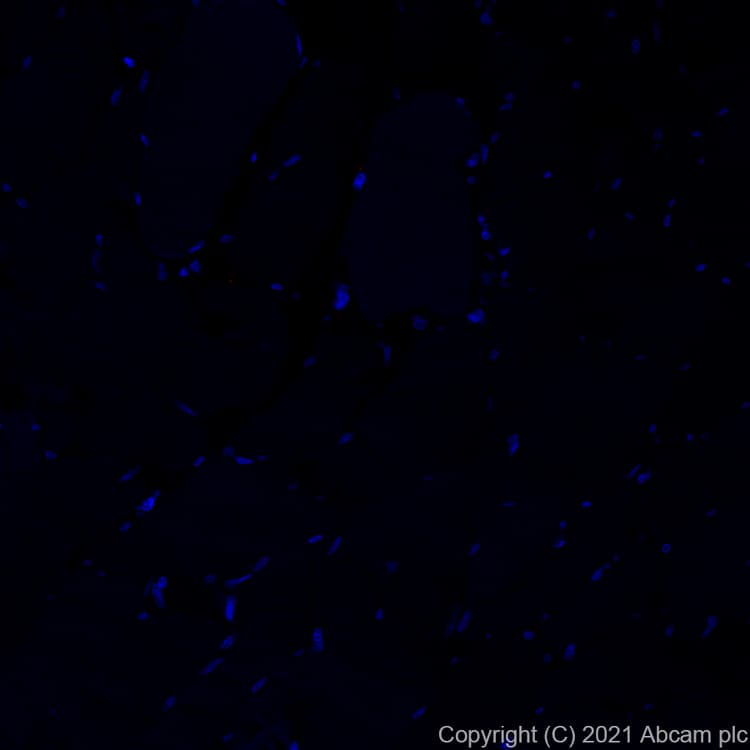

Alexa Fluor® 647 Anti-IGJ antibody [EPR23130-113](ab282706)

Rabbit Recombinant Monoclonal IGJ antibody - conjugated to Alexa Fluor® 647. Suitable for IHC-P and reacts with Human samples.

Applications ICC/IF, IHC-P

Species Reactivity Human

Conjugation Alexa Fluor® 647